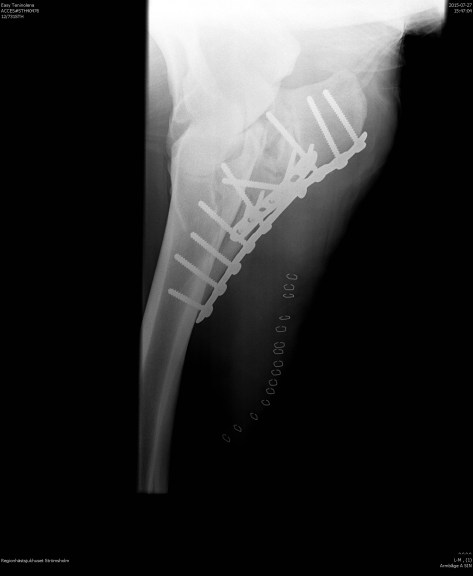

Maj 2015 skadar sig Lena då hon sparkas av en annan häst i hagen. Sparken träffar illa och det är tydligt att det rör sig om en allvarlig skada. Lena lyckas mirakulöst hoppa på tre ben in i transporten och förs till Evidensia specialisthästsjukhus Strömsholm. Röntgenplåtarna visar en krossfraktur av armbågen på vänster framben. Veterinär råder ägarna till konservativ behandling då det inte går att fästa eventuella skruvar i benet på grund alla fragment. Lena står i hängmatta två månader. Vid kontrollröntgen visar det sig att en av frakturerna ej läkt utan snarare förvärrats. Ägarna väljer efter second opinion från USA att låta operera hästen. Lena opereras i fyra timmar av Laura Hirvinen på Evidensia specialist hästsjukhus i Strömsholm. Operationen blir mycket lyckad, med två plattor och ett tiotal skruvar och Lena klarar den fantastiskt bra utan större ödem eller komplikationer.

När det blir dags för hästen att med assistans resa sig spricker operationssåret upp och Laura får sy igen det med Lena stående på gången, vilket innebär ytterligare någon timmes arbete. Sedan följer åter igen tid i hängmatta med bredspektrad antibiotika och som av ett mirakel blir såret aldrig infekterat utan läker fint. Under hela vårdtiden kämpar Lena på med gott humör. Ägaren Malou besöker henne dagligen på Strömsholms specialisthästsjukhus för att borsta henne och uppmuntra henne att kämpa vidare. Trots den långa konservativa behandlingen lyckas Lena behålla större delen av sin muskelmassa och äter med god aptit. När hon äntligen kommer ur hängmattan är det första hon gör att rulla sig. Personalen och Malou håller andan, men det går fint. Under den långa sjukhusvistelsen blev Lena personalens kelgris och det var inte ett öga torrt när Lena äntligen kunde lämna sjukhuset för att få komma hem. Väl hemma fortsatte den konservativa behandlingen med box och så småningom en mindre hage. Malou kommer aldrig glömma första ridturen i oktober 2015. Efter en gedigen rehabilitering där ägarna tar hjälp av Equirehab i Kvicksund som bland annat tillhandahåller vattenband, kan Lena återgå till karriären som terapi- och tävlingshäst maj 2016.